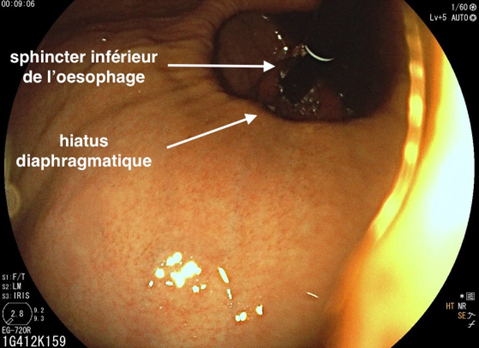

Depuis un an, elle rapporte des crampes d’estomac, notamment après des repas copieux, évoluant par périodes, ainsi qu’un pyrosis nocturne plusieurs fois par semaine. Elle a remarqué dernièrement une gêne thoracique lorsqu’elle boit de l’alcool et lors de ses séances de sport. Il n’y a pas de troubles du transit.

Le pyrosis et le syndrome postural sont des signes typiques de RGO.